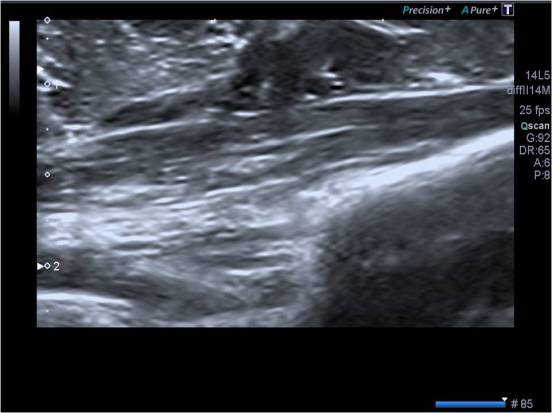

Ecográficamente el Nervio Cubital se verá en el corte transverso, redondo y ligeramente hipoecogénico debido al lugar donde se encuentra. En el corte longitudinal se verá como una «carretera» ligeramente curvado, hipoecogénico y con líneas centrales hiperecogénicas haciendo como «carriles», en este corte es muy complicado cogerlo íntegro,como la imagen que verás a continuación, tranquilx, solo es al principio.

Cortes e imágenes de normalidad:

Nervio ligeramente hipoecogénico y redondo.

Una imagen vale más que mil palabras, dos imágenes, figúrate…